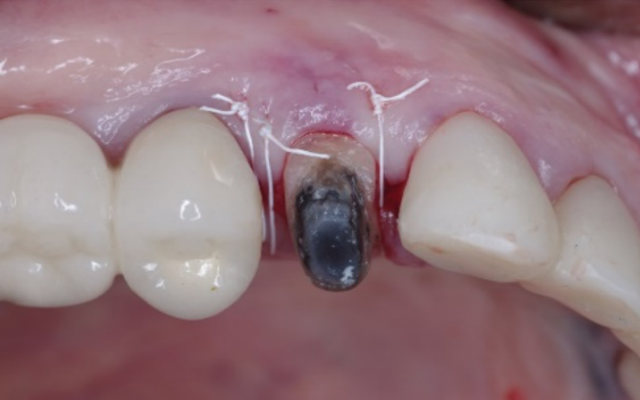

Functional crown lengthening is required if there is insufficient tooth structure to enable your dentist to provide a retentive and long-lasting restoration (Figures 9B & C). This may be because your tooth is broken, worn, or cracked or if there is extensive decay extending below the gum line.

Your periodontist will assess whether there is sufficient crown and root structure left to benefit from crown lengthening, and then advise you on the details of the procedure as well as the outcome. The crown lengthening procedure is normally carried out under local anaesthetic. It may involve removal of some of the gum and/or underlying bone. As it is a minor surgical procedure stitches are often used. The number of teeth that need treatment as well as the amount of gum repositioning will affect the healing time.